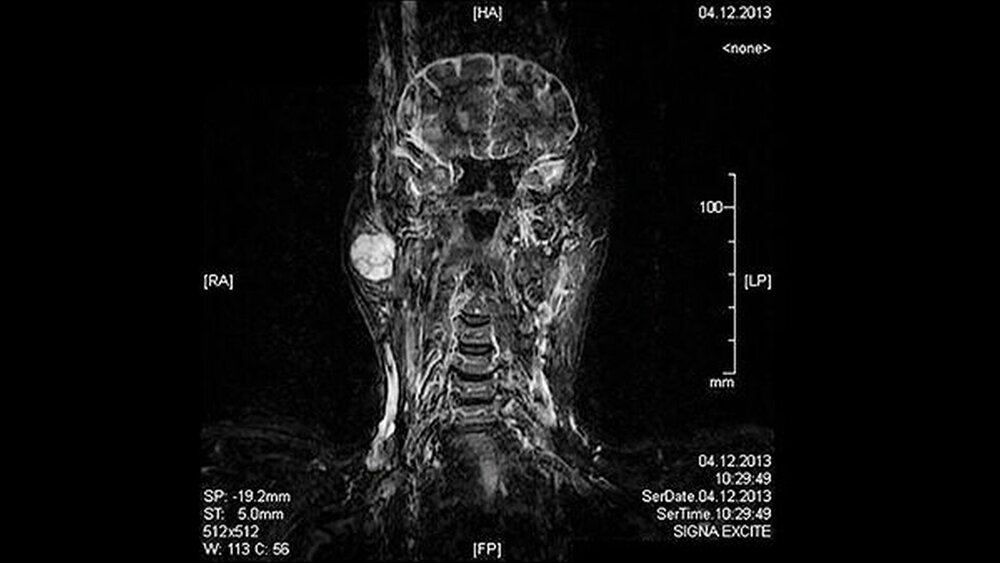

Eine 81-jährige Patientin wurde bei einer anamnestisch vor drei Jahren erstmals aufgefallenen und seither größenprogredienten Schwellung präaurikulär rechts (Abbildungen 1 bis 3) mit der Bitte um Weiterbehandlung an die Klinik für Mund-, Kiefer- und Gesichtschirurgie der LMU München überwiesen. Die alio loco durchgeführte bildgebende Diagnostik mittels MRT hatte einen abgegrenzten Prozess in der rechten Glandula parotidea gezeigt (Abbildungen 4 und 5). In der Zusammenschau der klinischen und der radiologischen Befunde wurde die Verdachtsdiagnose eines pleomorphen Adenoms im Bereich der Glandula parotis rechts gestellt.

Auch Risikofaktoren für das Auftreten eines pleomorphen Adenoms sind, abgesehen von einer höheren Inzidenz beim weiblichen Geschlecht, bisher nicht bekannt [Moeller et al., 2013]. Klinisch präsentiert sich der Tumor durch eine langsame und schmerzlose Größenprogredienz präaurikulär bei intraparotidealer Lokalisation. Palpatorisch zeigt sich eine harte Auftreibung im Bereich der großen Speicheldrüsen beziehungsweise im Bereich der kleinen Speicheldrüsen am Übergang vom harten zum weichen Gaumen als zweithäufigster Lokalisation für das Auftreten eines pleomorphen Adenoms. Die bildgebende Diagnostik der Wahl stellt die Magnet- resonanztomografie dar, die der Computertomografie vor allem bei einer palatinalen Lokalisation überlegen ist [Kakimoto et al., 2009].